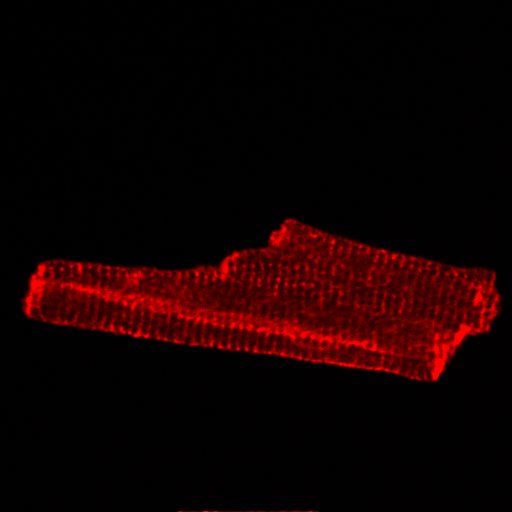

First image taken on our custom built muti-photon microscope (Cardiac myocyte)